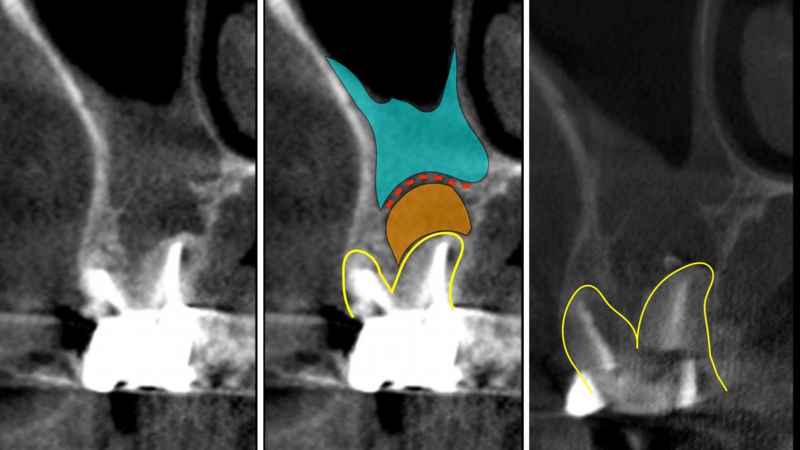

CTスキャン

2次元のレントゲンだけでなく、被爆線量の少ない歯科用CT検査を行う場合があります

根管治療を行う際、3次元的に病変の広がり、周囲組織のダメージ、また、根管の彎曲程度、方向などを知る事はとても重要です。

根管治療は、根の彎曲度合いや、根の形態(2つの根管が潰されて癒合していたり)等を前もって知る事で飛躍的に精度が上がります。現に他院のやり直しの根管治療では、根の見落としや根管を掃除する際に穿孔していたりという事を、頻繁に発見します。経験や手探りによる治療には限界があるという事ではないでしょうか?

マイクロスコープと併用する事により、入り口から出口までしっかり診査できますので、より安全、確実な処置が可能となります。

根管の中のロードマップです。

この組み合わせ3枚の写真はCT画像です。左の写真と真ん中の写真は同じものですが、わかりやすいように色を付けています。

黄色の線は根の外形です。

オレンジ色は、過去の根管治療の不備によりできた骨が吸収してしまった部分です。

赤の点線は、病変により破壊されてしまった上顎洞底(上顎洞と口の中を隔てる骨)の骨です。

水色は、それによって肥厚(腫れあがった)してしまった上顎洞粘膜です。

このような状態は2次元のレントゲンでは診断すらできません。CTを撮影することにより正確に診断ができ、それにあった処置法を選択する事が可能になります。

一番右の写真は処置直後で、MTAを用いて根管充塡し、治癒を待ちます。